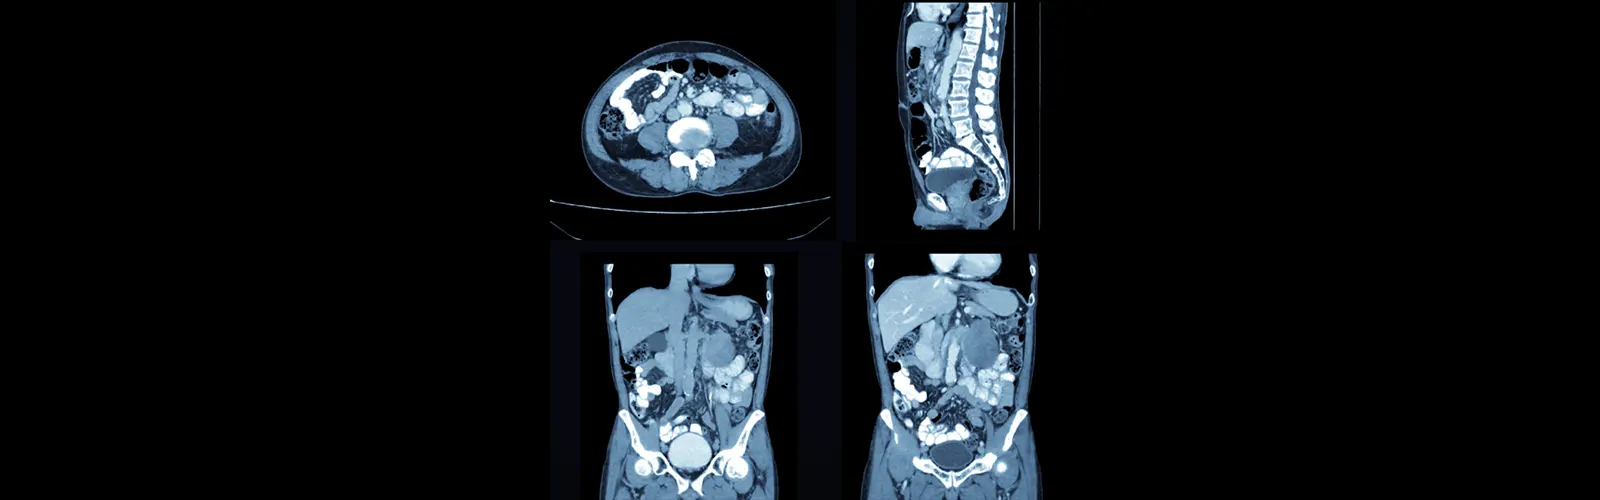

CECT is an acronym for "Contrast-enhanced Computed Tomography." It is a type of medical imaging that produces finely detailed pictures of the body's internal architecture by combining X-rays and a contrast agent.

CECT is an acronym for "Contrast-enhanced Computed Tomography." It is a type of medical imaging that produces finely detailed pictures of the body's internal architecture by combining X-rays and a contrast agent. A patient is placed on a table and pushed through a doughnut-shaped device called a CT scanner during a CECT scan. An image of the body's cross-section is created using X-rays captured from various angles while the table goes through the scanner.

A substance known as a contrast agent is injected into the patient's vein to highlight specific body areas or anomalies. It makes it easier for professionals to recognize several medical problems by helping to distinguish between normal and diseased tissues. To detect and monitor conditions like cancer, infections, wounds, and vascular issues, CECT scans are routinely used.